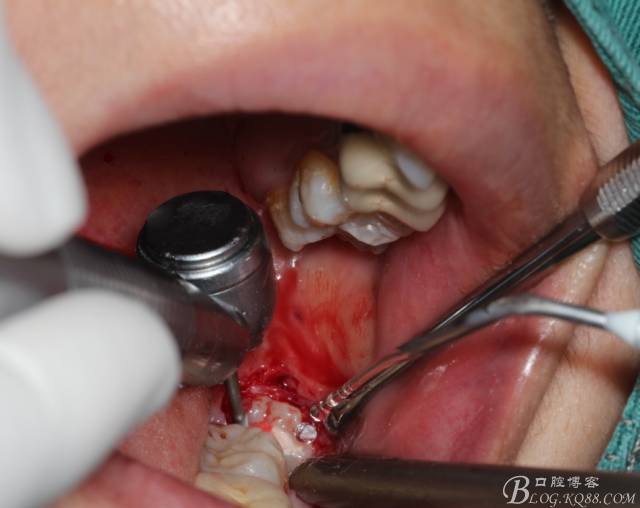

切開(kāi):角形切口,這個(gè)位置切開(kāi)我喜歡更易操作12#刀。

鈍性翻辨露冠